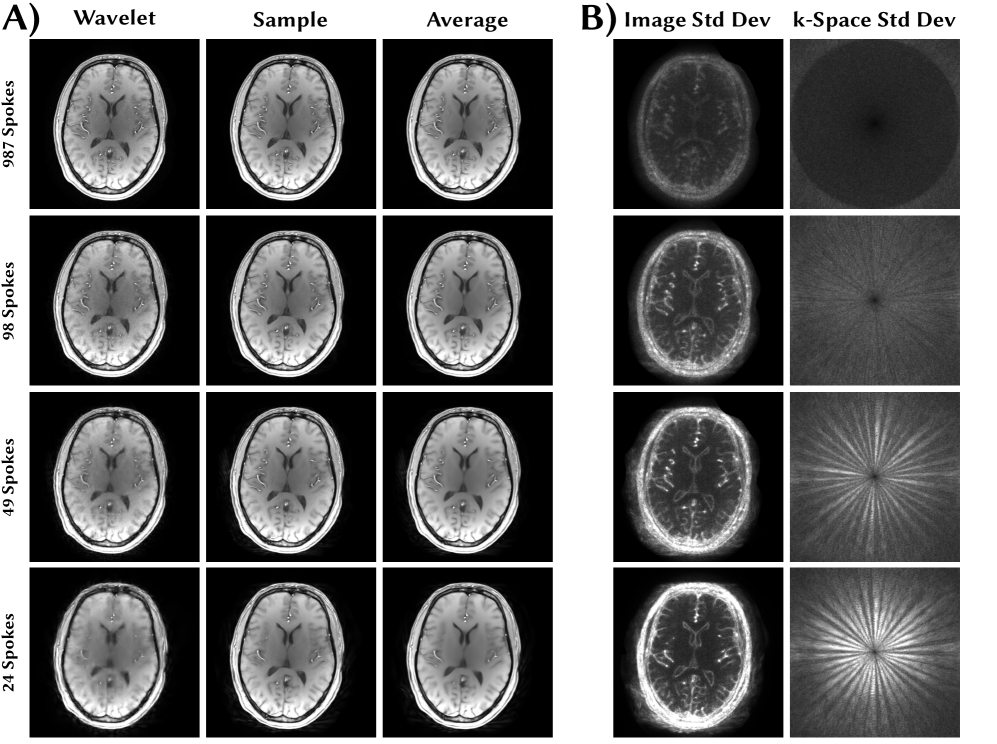

Figure 5: Brain image reconstructed from radially acquired FLASH data using different undersampling factors. A: Reconstruction with 1\ell_{1}-Wavelet regularization, a single sample from the posterior with exact likelihood and the average of ten samples. B: Pixel-wise standard deviation map in image space and k-space.

The results of the non-Cartesian reconstruction are shown in Figure 5. While the individual samples are rich in details even in the 40-fold undersampled case, the average is slightly blurred. The pixel-wise standard deviation shows high uncertainty in regions containing small vessels.